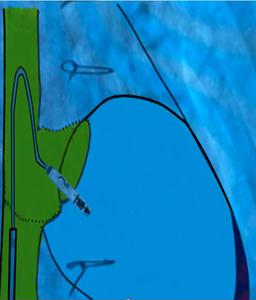

Figure 8. Schematic representation of the catheter- based approach

Figure 9. Schematic overlay showing the optimal angle

of delivery for device implantation in an anatomically restricted right ventricle

At the junction of the superior vena cava and right atrium, maximal deflection of the distal catheter segment was applied, followed by slight retraction, creating an acute 70–90° bend resembling a “hockey stick.” This configuration shortened the working length, allowing maneuverability in the restricted RV cavity. Crossing the tricuspid valve was guided by RAO 30° and LAO 40° projections to ensure septal alignment. In the apical-septal region, contact mapping (with the helix unreleased) confirmed acceptable parameters (R-wave ≥5 mV, threshold ≤1.0 V at 0.4 ms, impedance 400– 1500 Ω). Upon satisfactory values, the device was screwed into the septum with 1.5 turns. Perpendicular positioning was confirmed in orthogonal views, followed by a tug test. Repositioning was feasible if parameters were suboptimal.